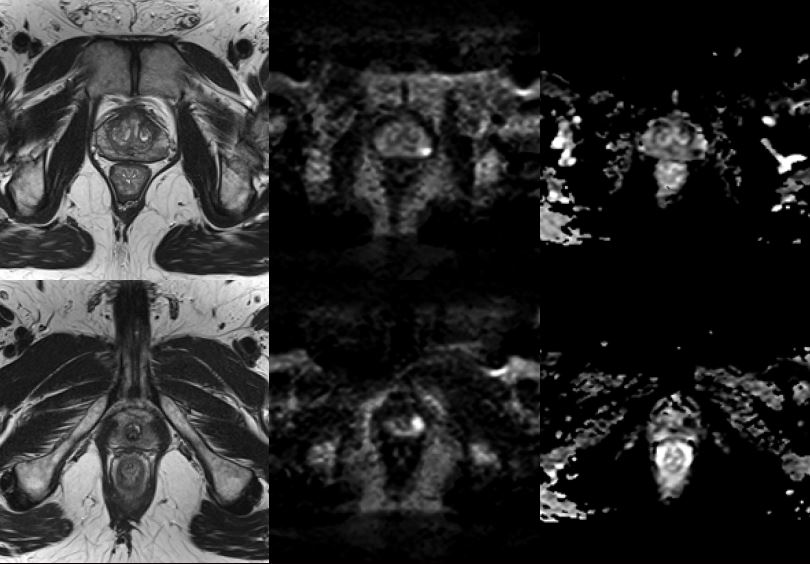

Верхній ряд: T2-зважене, b2000 DWI та ADC демонструють PIRADS 4 ураження розміром 8 мм зліва посередні периферичної зони.

Нижній ряд: T2-зважене, b2000 DWI та ADC демонструють PIRADS 4  ураження розміром 6 мм зліва вверху периферичної зони